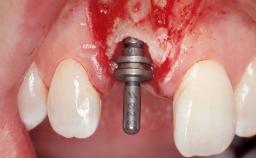

Immediate Flapless Placement of an Implant in a Maxillary Right Lateral Incisor Site

This 43-year-old male patient, a non-smoker, came to our practice because of a fracture of tooth 12 caused by a bicycle accident. Due to the combined para- and infrabony crown and root fracture, tooth extraction, and subsequent implant placement were suggested to the patient as the therapy of choice. The patient had high esthetic expectations with regard to the treatment outcome and asked for an immediate fixed provisional restoration. His individual esthetic risk profile summed up to a medium esthetic risk.

Placement Protocol Immediate implant placement

Tooth Site Maxillary incisor or canine

Socket Morphology Single-root socket

Socket Integrity Sufficient, with intact bone walls

Bone Volume Sufficient, with intact walls

Loading Protocol Immediate